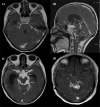

Neuro-ophthalmic features are a known association in tuberculosis, especially common in central nervous system tuberculosis (CNS-TB). They are mostly the result of the visual pathway and/or ocular motor and other cranial nerve involvement. Furthermore, toxic optic neuropathy and paradoxical response to anti-tubercular drugs (ATT) are also not uncommon. The etiopathogenesis is by the complex interplay of various factors like exudates, vasculitis, arachnoiditis, presence of tuberculomas, hydrocephalus, brain infarcts and/or immune-mediated reaction. The entity often poses a diagnostic dilemma for the ophthalmologists/neuro-ophthalmologists and may lead to irreversible vision loss. The presence of neuro-ophthalmic features not only affect the visual outcome but are also predictors of systemic morbidity of the disease. Therefore, understanding and knowledge about this entity are necessary for the comprehensive management of the disease. While various forms of TB including CNS-TB have been well-dealt with in literature, little is discussed specifically about the neuro-ophthalmic manifestations of tuberculosis. Therefore, the purpose of this review is to highlight current understanding of the types of neuro-ophthalmic involvement in tuberculosis, its etiopathogenesis, diagnosis and management.